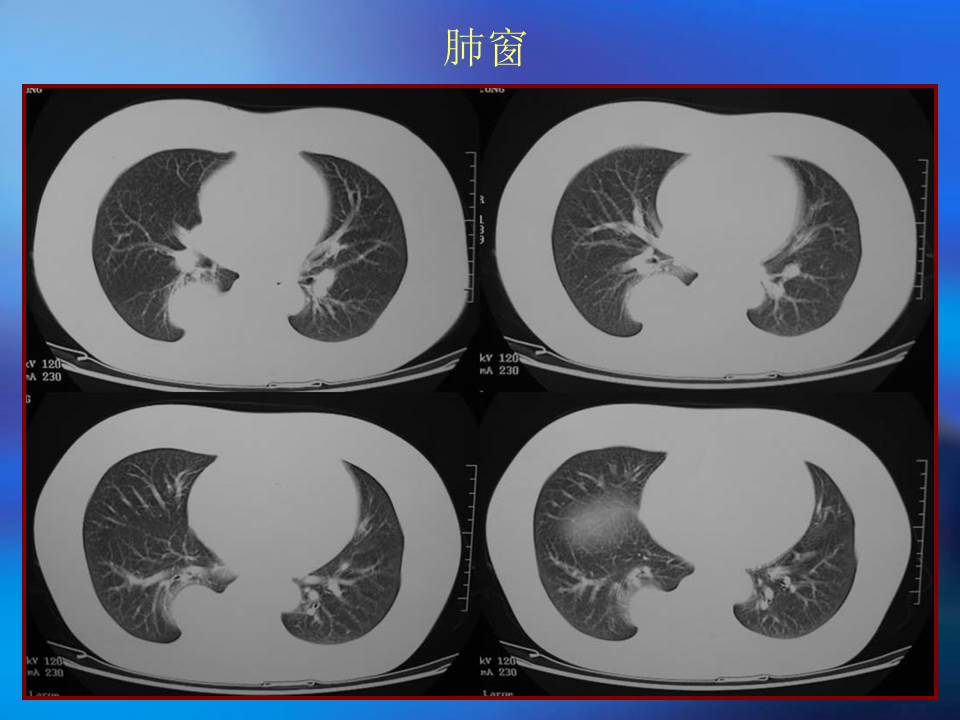

肺良性肿瘤